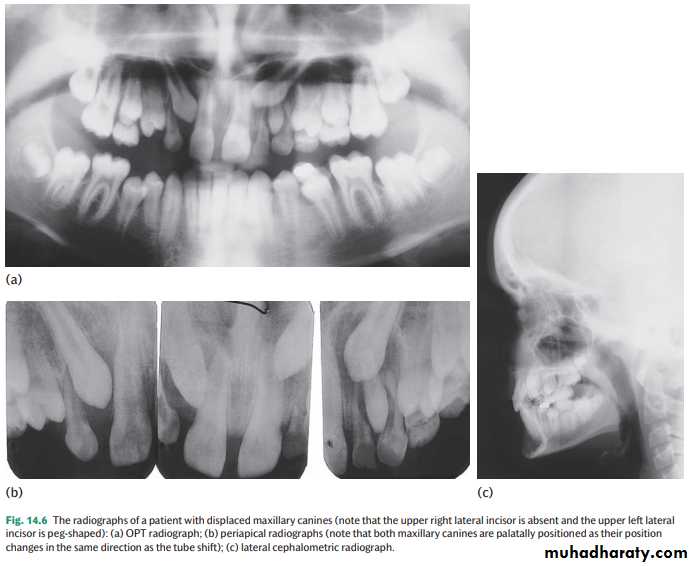

• Dental panoramic tomogram (OPG or DPT).This film gives a good overall assessment of the development of the dentition and canine position. However, this view suggests that the canine is further away from the midline and at a slightly less acute angle to the occlusal plane, i.e. more favourably positioned for alignment, than is actually the case ( Fig. 14.6 a). This view should be supplemented with an intra-oral view.

The principle of parallax can be used to determine the position of an unerupted tooth relative to its neighbours. To use parallax two radiographs are required with a change in the position of the X-ray tube between them. The object furthest away from the X-ray beam will appear to move in the same direction as the tube shift. Therefore, if the canine is more palatally positioned than the incisor roots it will move with the tube shift ( Fig. 14.6 b). Conversely, if it is buccal it will move in the opposite direction to the tube shift. Examples of combinations of radiographs which can be used for parallax include two periapical radiographs (horizontal parallax)

This view is useful for assessing the prognosis of a retained deciduous canine and for detecting resorption ( Fig. 14.6 b).•Occlusal view x- ray.

For accurate localization this view should be combined with an anteroposterior view (e.g. an OPT) ( Fig. 14.6 c).• Cone beam computerized tomography (CBCT). Due to the increased radiographic dose, most orthodontists restrict CBCT to those ectopic canines where accurate localization has not been possible with conventional views and/or root resorption of adjacent teeth is suspected (see Fig. 5.17 ).